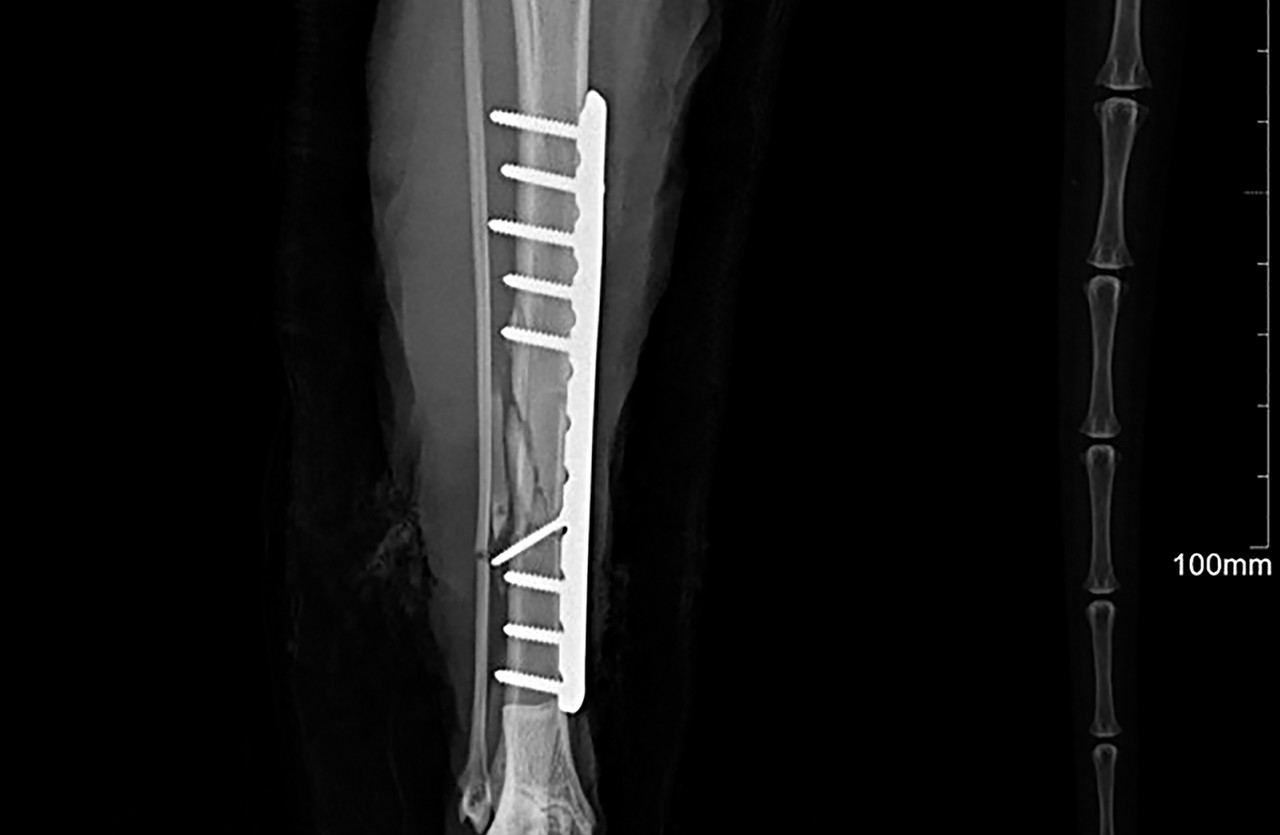

플레이트 스크류 장비

SYNTHES / biortho / Doiff / Able

골절된 뼈를 고정하기 위해 사용하는 의료용 자재입니다.

체내에 부착되고 체형, 뼈 구조, 골절 형태 등에 따라 맞춤형으로 각각 다른 종류를 사용하게 됩니다.

휴 동물의료센터에서는 안전하고 효과적인 치료를 위해 프리미엄급 플레이트 스크류를 사용하고 있습니다.

플레이트 스크류 장비 SYNTHES / biortho / Doiff / Able 골절된 뼈를 고정하기 위해 사용하는 의료용 자재입니다. 체내에 부착되고 체형, 뼈 구조, 골절 형태 등에 따라 맞춤형으로 각각 다른 종류를 사용하게 됩니다. 휴 동물의료센터에서는 안전하고 효과적인 치료를 위해 프리미엄급 플레이트 스크류를 사용하고 있습니다.